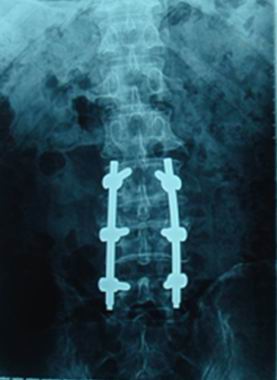

中國科學院金屬研究所與第四軍醫大學、中國醫科大學等單位針對Ti2448合金的醫療應用開展了持續的合作研究,在材料、表面生物活性處理、體外細胞和體內動物實驗等方面取得了大量詳實可靠的數據;研發了創傷類彈性接骨板、彈性髓內針和脊柱類彈性固定系統等產品,并進行了生物力學表征、疲勞壽命檢測和動物實驗。以上合作研究成果為推動Ti2448合金的醫療應用提供了重要的科學基礎。

中國科學院金屬研究所自2005年起與威高骨科材料有限公司合作,先后開展了植入器械的研發和產品注冊證的申報工作。2006年,金屬所建立了Ti2448合金材料的企業標準,威高骨科采用Ti2448合金加工了彈性接骨板和脊柱固定系統,并分別報送國家食品藥品監督管理局天津醫療器械監督檢驗中心檢驗,2008年成功通過了生物學安全性考核。2008年和2009年,Ti2448合金接骨板和脊柱固定系統分別在山東大學附屬齊魯醫院、山東省中醫院以及中國醫科大學附屬第一臨床醫院、吉林大學附屬第二臨床醫院開展了臨床試驗。目前,兩類產品的臨床試驗已經成功完成,威高骨科材料有限公司已經向國家食品藥品監督管理局申報產品注冊證。